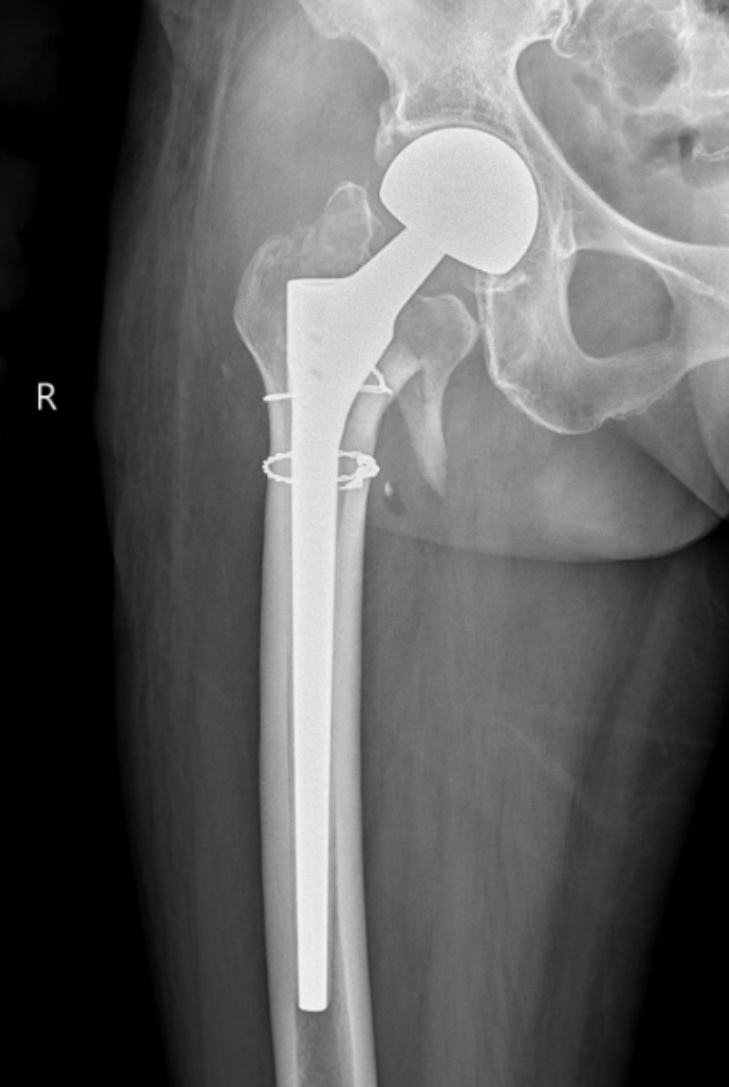

典型病例影像学表现见图1~10。图1为86岁女性右侧股骨转子间骨折(Evans Ⅲ型)患者,术前X线示骨折断端部分错位,术后X线示骨折位置可以及假体位置良好;图2显示了一名81岁男性患者,诊断为左侧股骨转子间骨折,类型为Evans V型,合并股骨干陈旧性骨折。患者接受了生物型加长柄半髋关节置换手术,并进行了股骨近端的钢丝捆扎内固定。术后X线示假体位置良好,股骨近端予钢丝捆扎固定;图3为87岁女性左侧股骨转子间骨折(Evans V型)患者,术后X线示假体位置良好,股骨大小转子骨折位置可,钢丝捆扎固定在位有效;图4为75岁女性左侧股骨转子间骨折(Evans V型)患者,术前X线示左侧股骨转子间骨折PFNA术后、骨折未愈合、内固定断裂。术后假体匹配良好,股骨近端钢丝内固定稳定可靠;图5为75岁男性左侧股骨转子间骨折(Evans IV型)患者,术后股骨大转子出现轻度位移,假体位置正常。图6为87岁男性左侧股骨转子间骨折(Evans V型)患者,给予DAA入路加长柄半髋关节置换,术前X线片,清晰地显示出左侧股骨转子间的骨折情况,术后X线影像,显示股骨的大小转子骨折位置良好,钢丝内固定装置在位稳定,假体位置良好;图7为77岁女性右侧股骨转子间骨折(Evans V型)患者,术前X线片显示右侧股骨转子间存在骨折且股骨大小转子均有累及和移位,术后X线片显示股骨小转子轻度移位,内固定装置位置稳定,假体位置良好;图8为70岁男性左侧股骨转子间骨折(Evans III型)患者,术前的X线片,清晰地显示了左侧股骨转子间的骨折情况,股骨近端髓腔钙化灶,术后假体位置满意;图9为77岁女性右侧股骨转子间骨折(Evans V型)患者,术前X线片,显示右侧股骨转子间及转子下部位骨折情况。术后假体匹配良好;图10为71岁男性右侧股骨颈骨折(Evans IV型)患者,术前X线片,显示右股骨转子间骨折的情况;术后X线表明股骨的大转子和小转子骨折位置保持良好,内固定装置稳固,术后假体位置正常。

Figure 1. 86-year-old female patient with right intertrochanteric fracture of femur (Evans type III). (a) Before surgery; (b) After surgery

1. 86岁女性右侧股骨转子间骨折(Evans Ⅲ型)患者。(a) 术前;(b) 术后